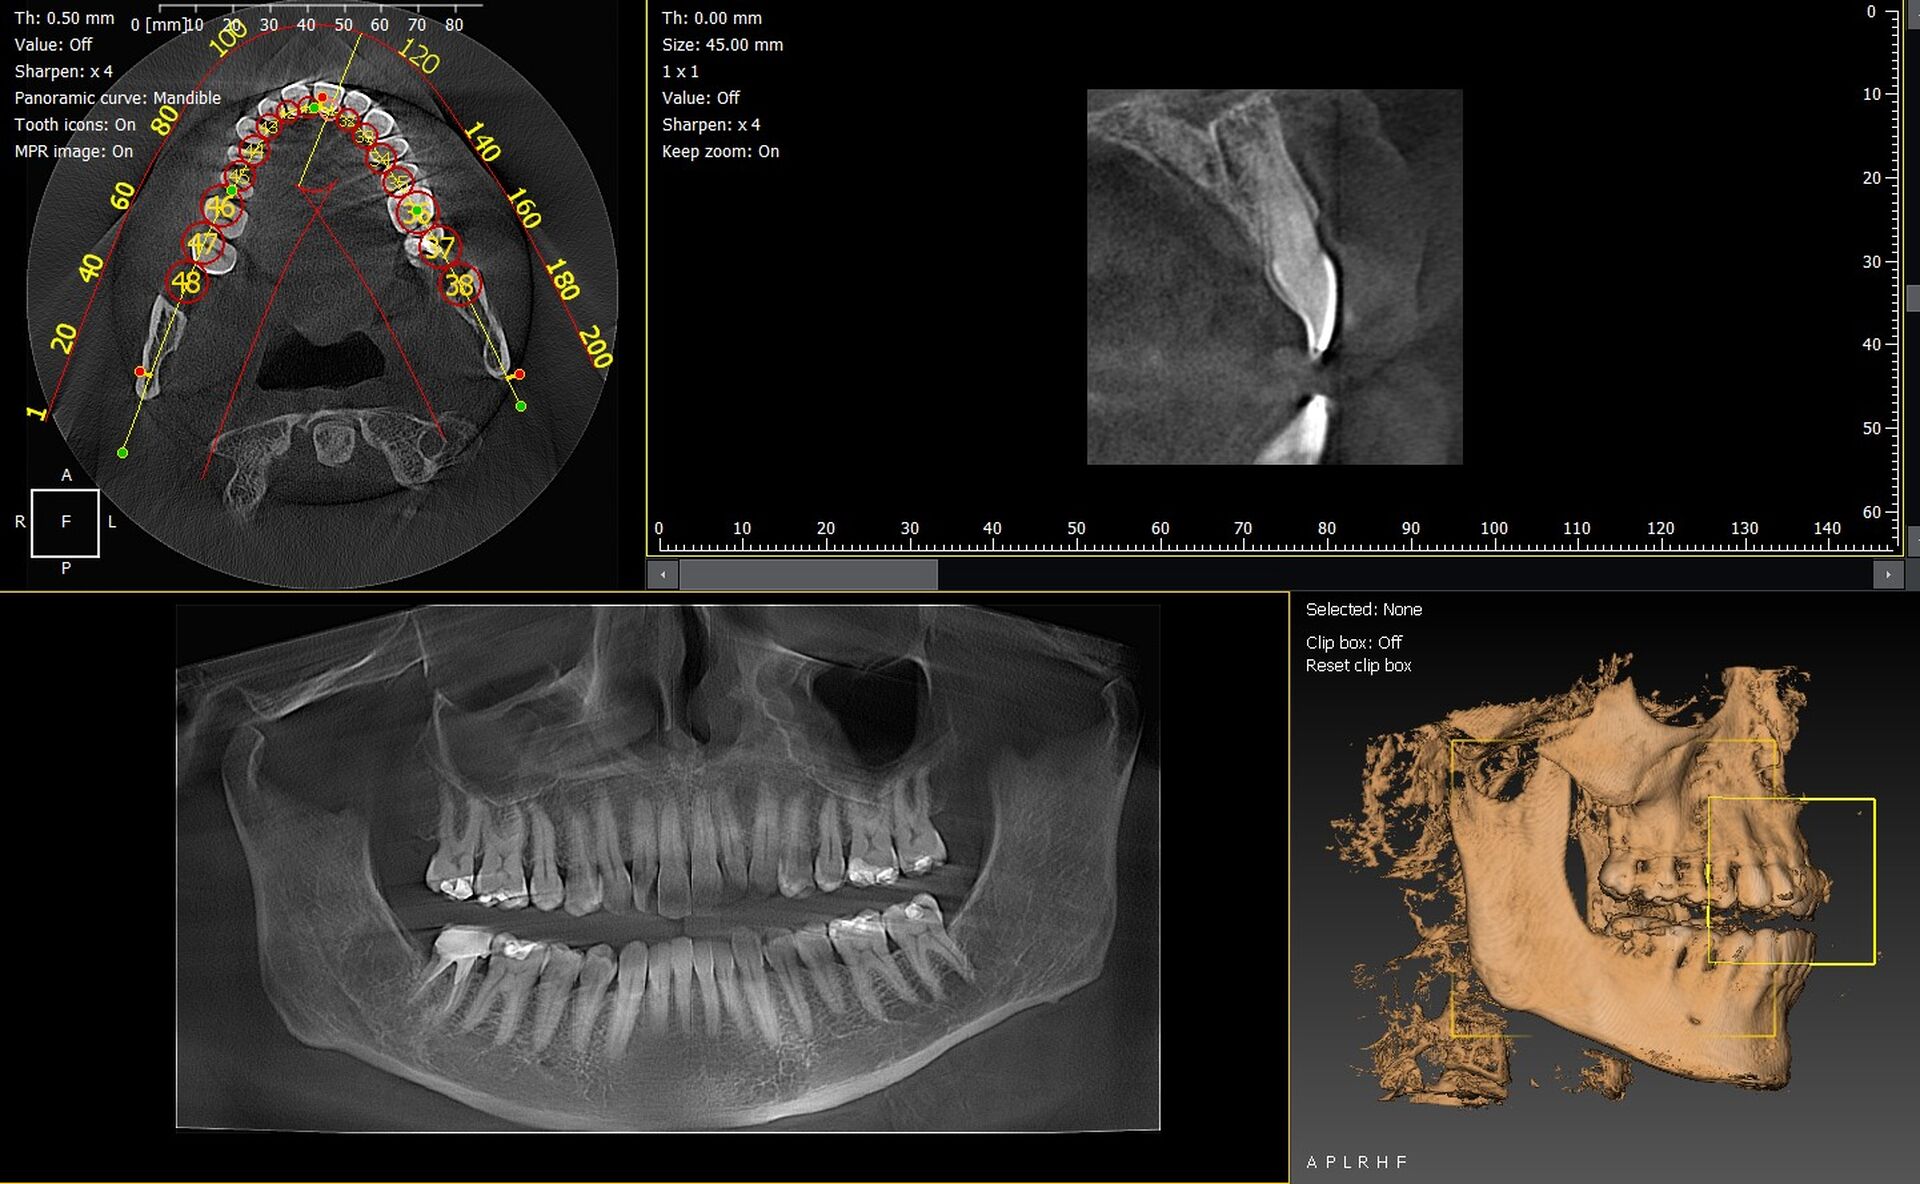

Les cabinets dentaires d’Antibes et de l’ensemble des Alpes-Maritimes (06) cherchent à renforcer la précision de leurs diagnostics grâce à des solutions d’imagerie 3D modernes et performantes. Les panoramiques CBCT 3D VistaVox de Dürr Dental et l’Owandy I-Max 3D s’imposent aujourd’hui comme des références pour une acquisition rapide, fiable et parfaitement adaptée aux besoins cliniques.

VistaVox 3D : une imagerie ultra précise

Le Dürr Dental VistaVox offre un volume conçu pour épouser l’arcade dentaire, permettant :

• une analyse fine en implantologie,

• une vision détaillée en endodontie,

• un diagnostic chirurgical renforcé,

• une réduction de dose grâce à un champ optimisé.

Sa qualité d’image place cet appareil parmi les plus performants du marché.